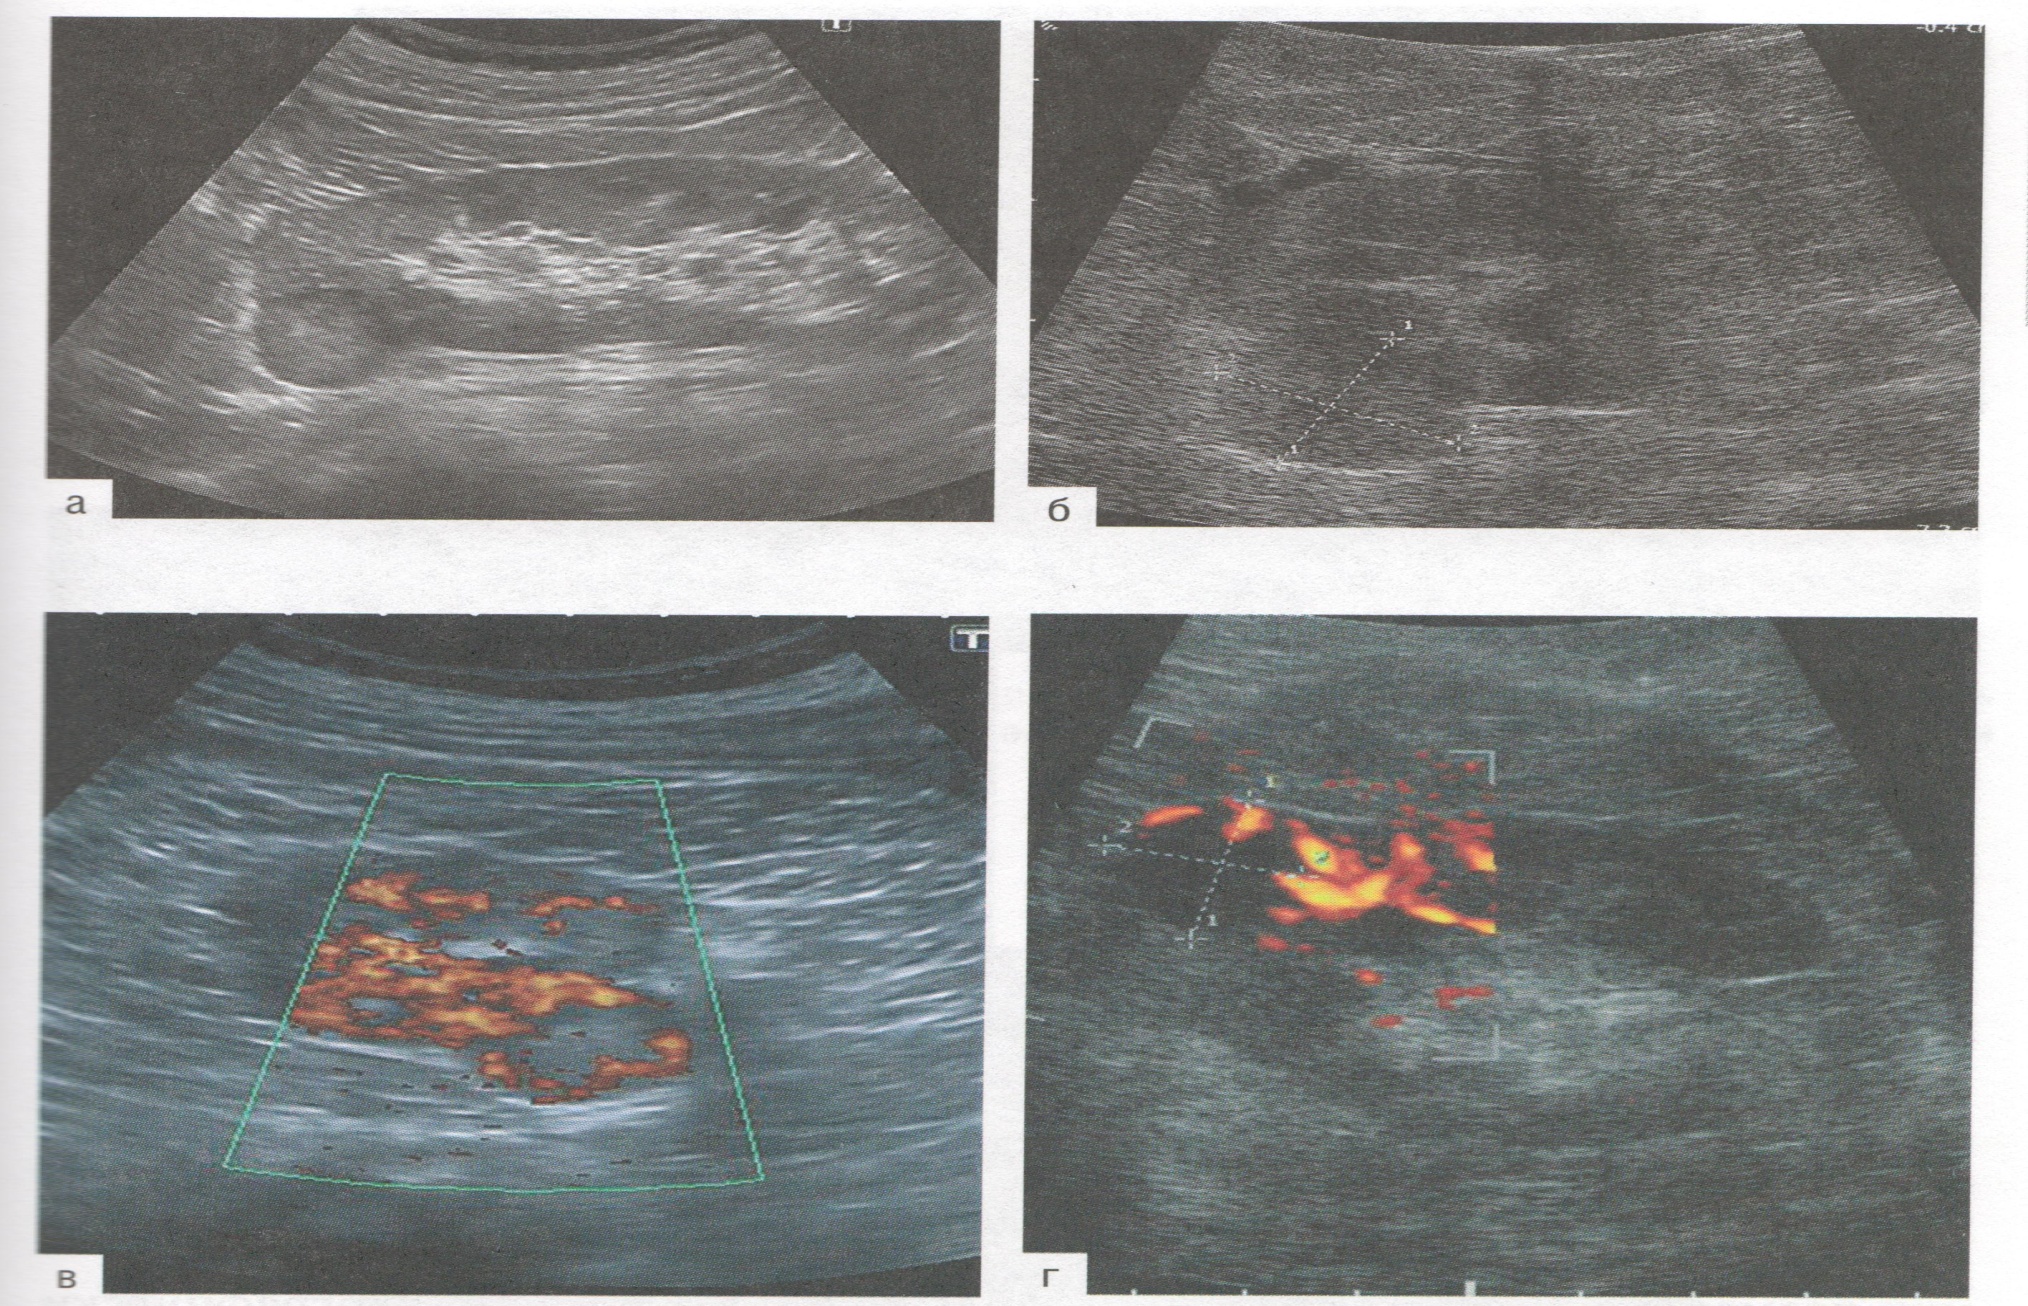

Plasentanyň aşakda ýerleşmegi

27

1